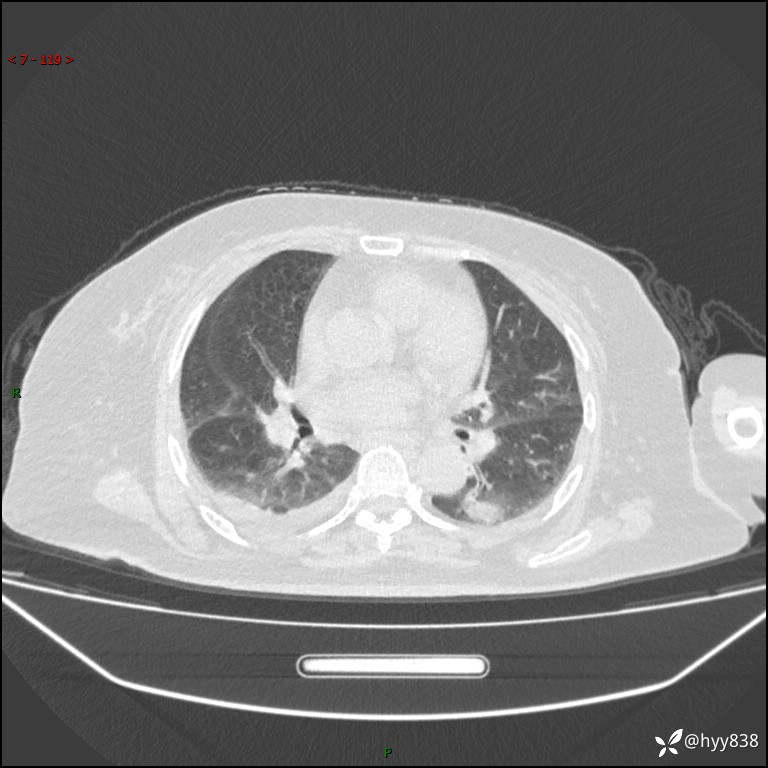

胸部 CT平扫、

颅脑MRI(T2WI+DWI)